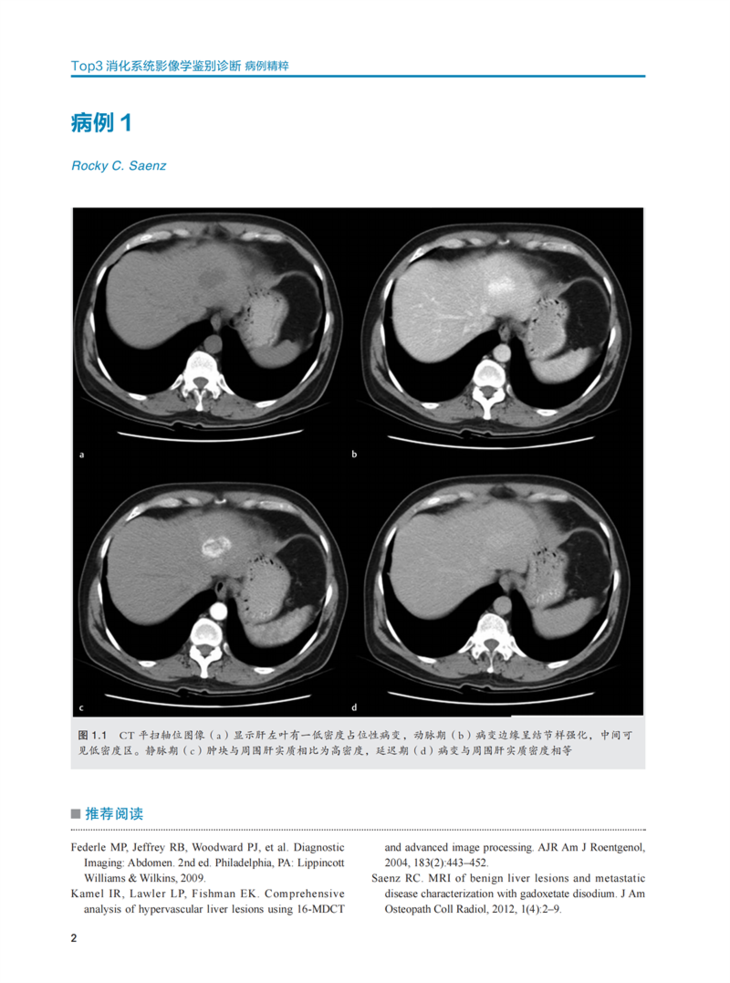

·200 幅高质量影像图片辅助诊断。

·150例精选病例,涉及X线、CT、超声、MRI、钡餐透视等成像方式。

《Top3胃肠道影像学鉴别诊断》包括肝胆、胰腺和脾脏、胃肠道、肠系膜和血管、腹壁和软组织5个部分的150个病例。与其他Top 3系列的图书一样,本书的重点是基于病例的鉴别诊断,必要的病例中还补充了X线检查方面的内容。基于特定临床病史或影像学表现的 “Top 3”鉴别诊断是临床诊治的重要参考因素,这些精心挑选的病例涵盖了所有影像学成像方式,并且进行了胃肠道成像方面高质量和全面的阐述,对培养影像学医生的诊断思维和丰富知识储备有非常重要的作用。本书可以作为住院医师和主治医师的影像快速参考书。